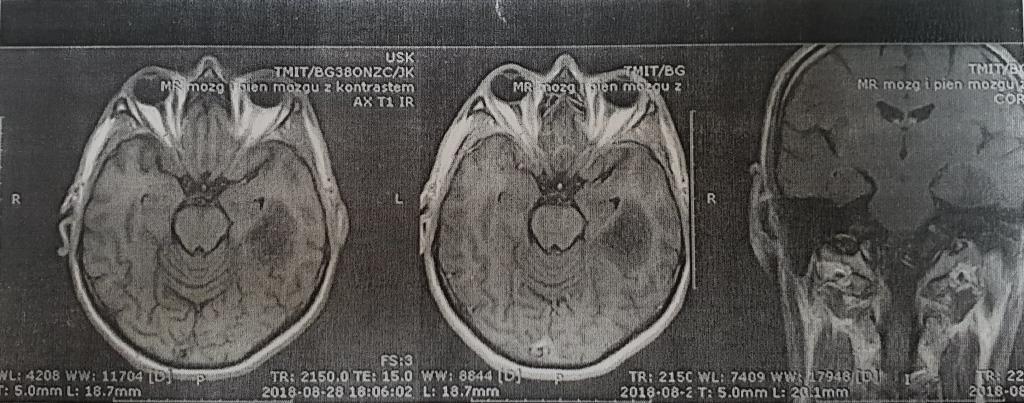

Pytanie 120

Obrazy MR dotyczą 37-letniego mężczyzny, u którego wystąpił napad padaczkowy. Przedstawiają przekrój osiowy głowy w badaniu rezonansu magnetycznego bez wzmocnienia kontrastowego i ze wzmocnieniem oraz przekrój w płaszczyźnie wieńcowej (czołowej), również ze wzmocnieniem gadoliną. Najbardziej prawdopodobne rozpoznanie to: